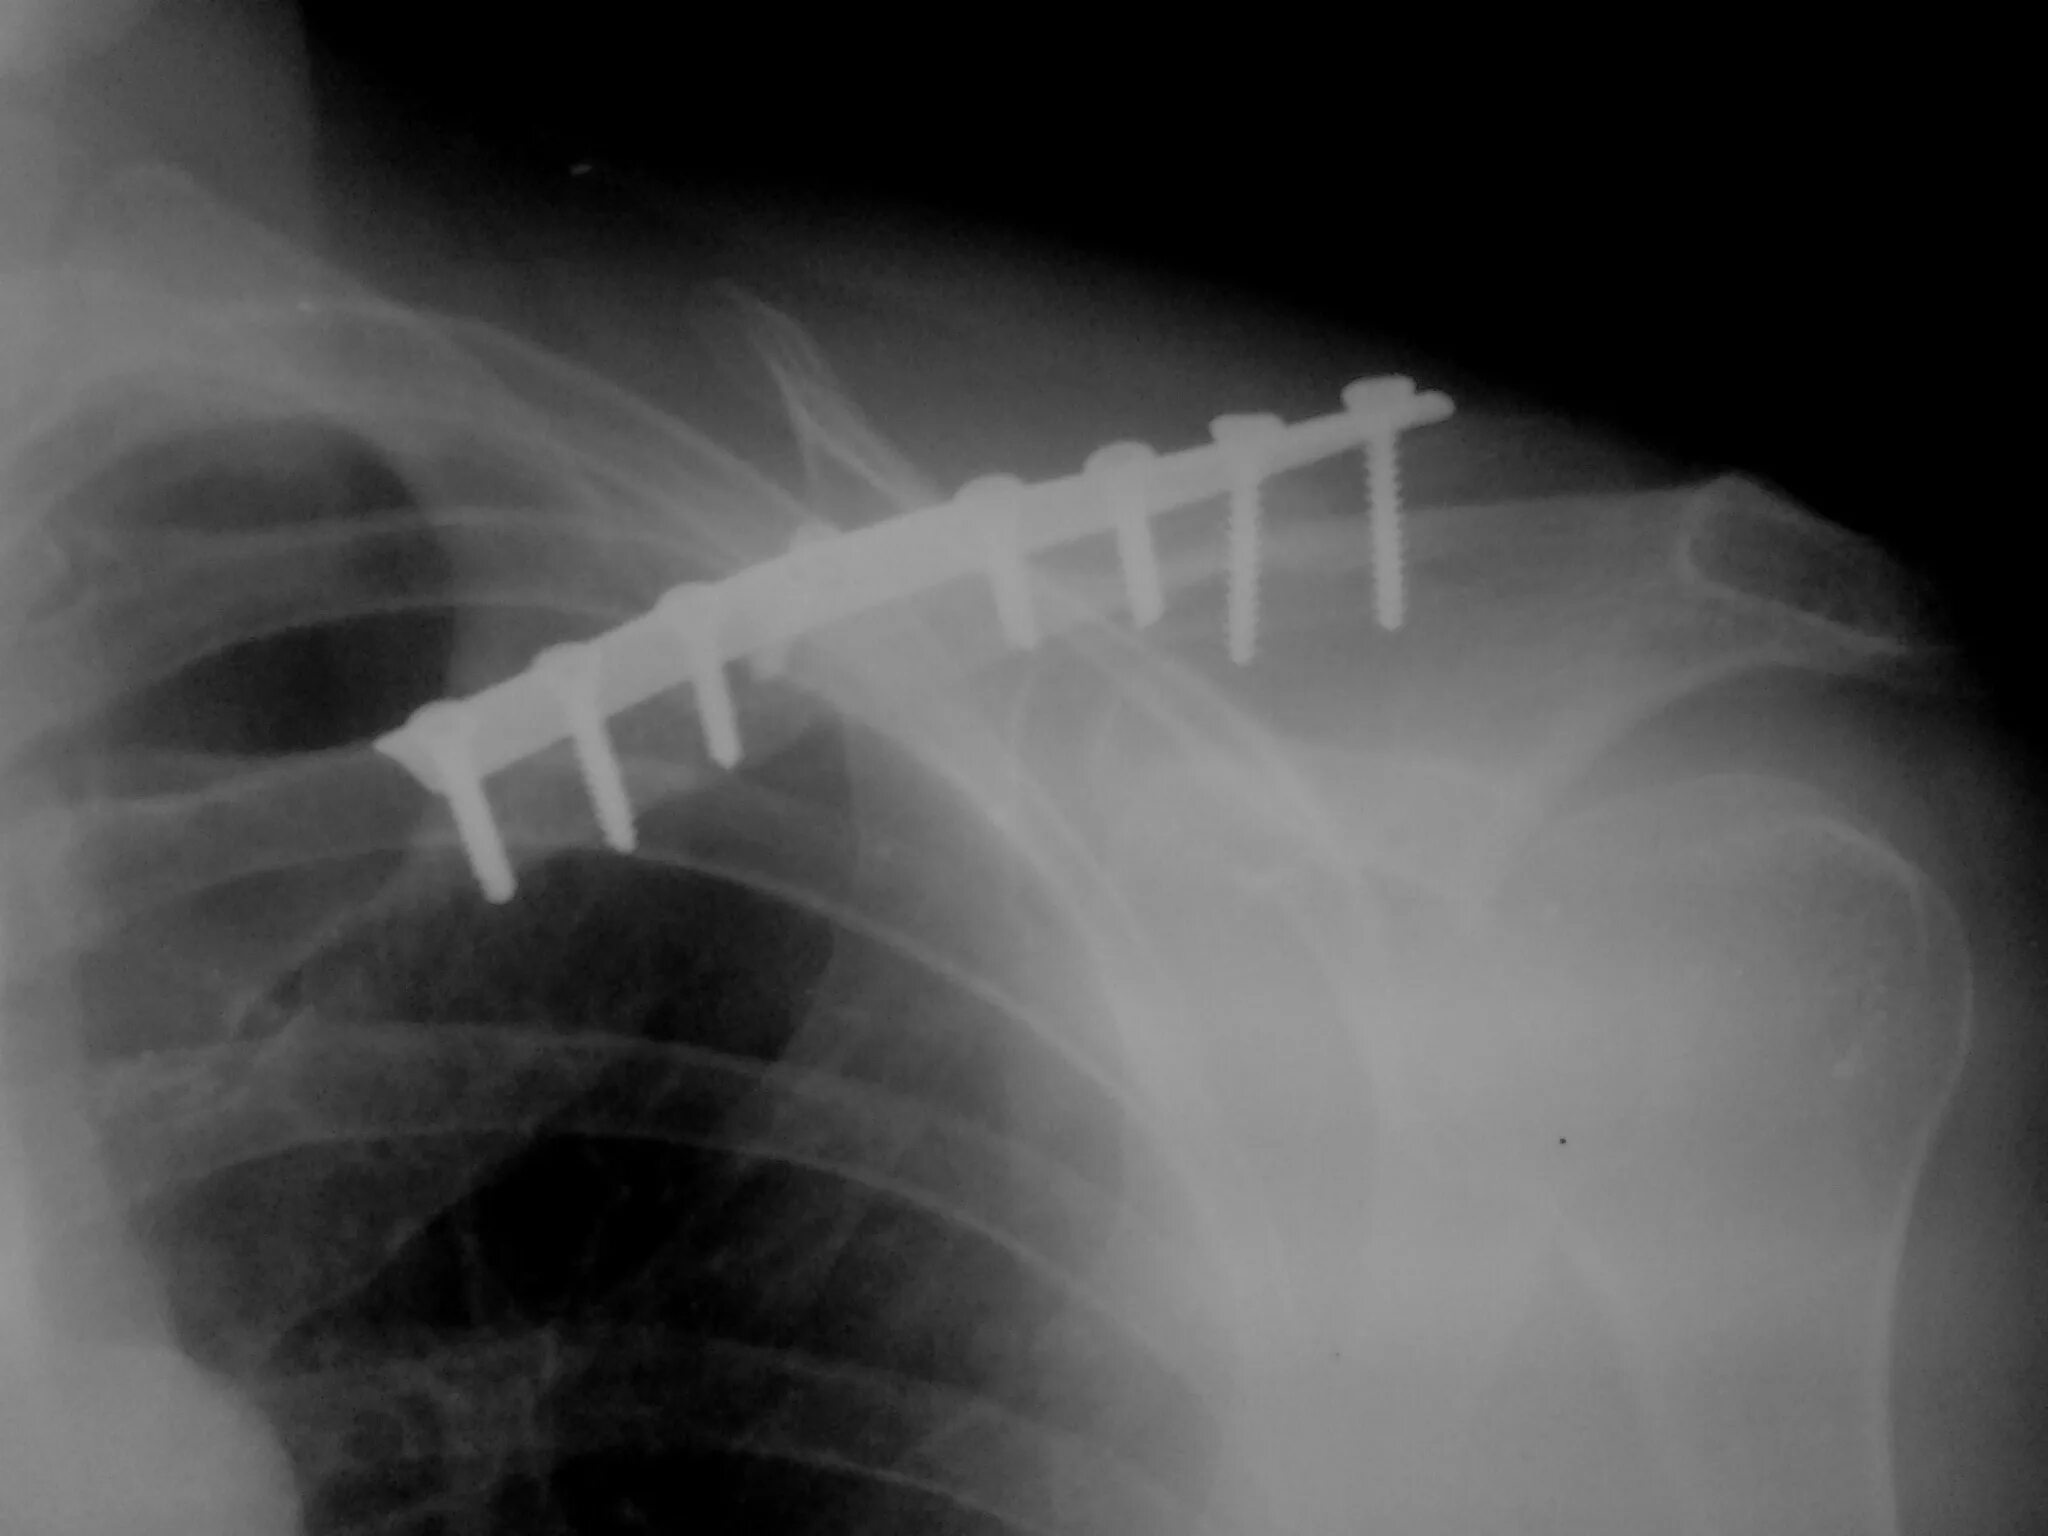

Сколько срастается ребро при переломе